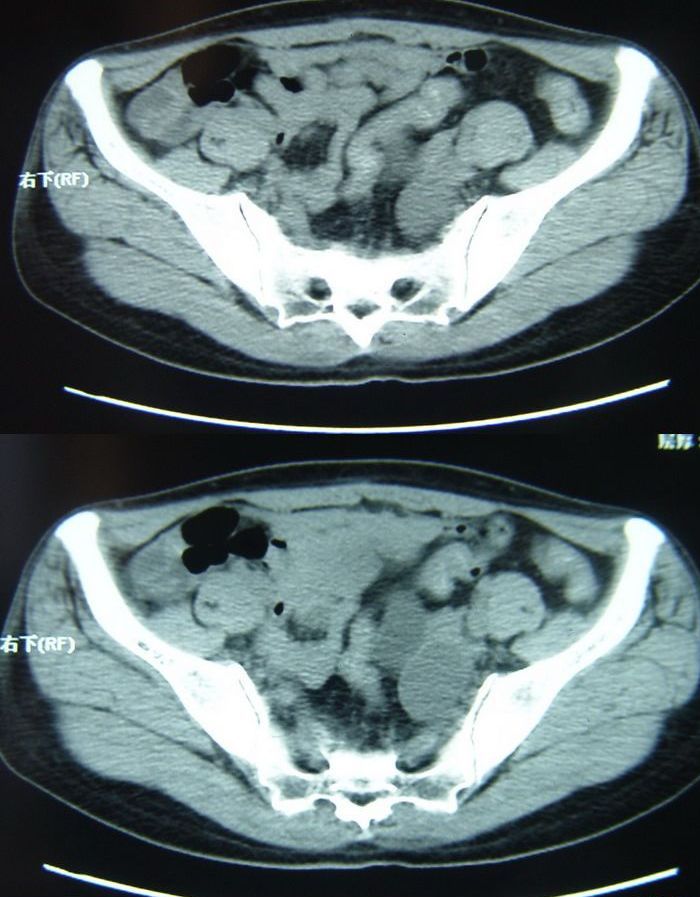

以下是今天的增强片,大家可以看看:

右髂骨见一类圆形略高密度区,似见分层,骨质破坏不明显

考虑良性病变,以动脉瘤样骨囊肿可能性大

右侧髂骨后缘囊状膨胀性骨质改变,无明显骨间隔,周围无明显硬化及骨膜反应,周围软组织无异常,相邻骨组织密度增高,考虑:动脉瘤样骨囊肿可能,要注意与骨巨细胞瘤及转移瘤鉴别。

囊性;密度均;未见分格;骨囊肿

右侧髂骨膨胀性骨质破坏区 囊内密度尚均匀 骨巨细胞瘤可能性大 动脉瘤样骨囊肿不除外 建议mr观察囊内成分明确诊断 左侧附件区包裹性积液

右侧髂后上棘局限性囊状骨质破坏,大部分界清,似见轻度硬化边,内无分格及钙化,病灶上部局部显示模糊。考虑;骨巨细胞瘤可能大,不除外abc。另可见子宫肌瘤术后子宫缺如。

临床和影像学表现:女性患者46岁,有子宫肌瘤手术病史。影像所见可见残余宫颈部分,左右附件未见新生物;右髂骨翼后端囊状膨胀性骨破坏,囊性部分感觉有强化(楼主标上增强前后的ct值就很好了),未见明确的液—液平面,周边硬化不明显或轻度硬化。

分析:患者年龄46岁,没有明确外伤病史,病变呈膨胀性骨破坏,囊性部分未见明确的液—液平面,周边硬化不明显。综合分析该病例比较符合骨巨细胞瘤,不太符合动脉瘤样骨囊肿。

诊断:1、首先考虑骨巨细胞瘤;2子宫肌瘤术后改变